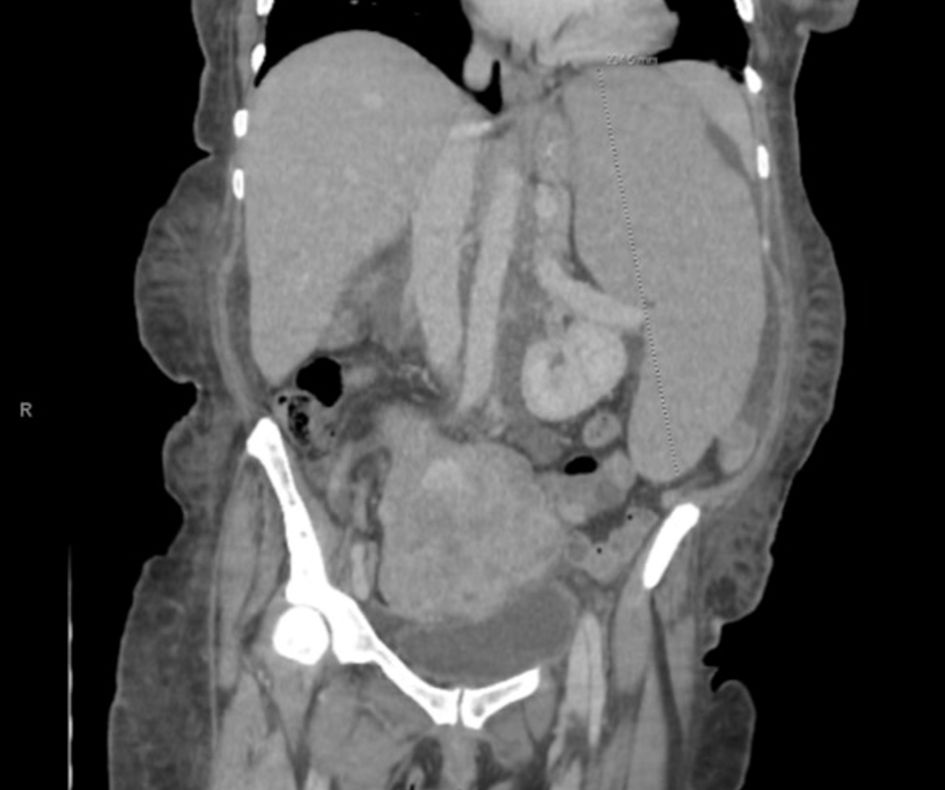

Complete blood count (CBC) showed a white blood cell count of 584 × 109/L with absolute lymphocytes of 513 × 109/L, hemoglobin at 2.7 g/dL, mean corpuscular volume (MCV) of 108.7 fL, and platelets at 60 × 109/L. The patient had no previous baseline laboratory studies available for comparison. Iron studies, ferritin, haptoglobin, vitamin B12, and folate were within normal limits. Basic metabolic profile and liver function tests were normal. A peripheral smear was obtained at outside hospital prior to transfer to our hospital, which showed some immature/atypical lymphoid cells, not thought to be blasts, and no presence of Auer rods. Viral studies including HTLV 1/2 antibody, hepatitis, Epstein-Barr virus (EBV), and cytomegalovirus (CMV) were negative. CT scan of the abdomen and pelvis revealed diffuse lymphadenopathy, splenomegaly, and lobulated uterus with partially calcified and heterogenous appearing fibroids (Figs. 1 and 2). The presence of fibroids was confirmed with transabdominal ultrasound, which showed enlarged uterus with multiple masses again most fitting with fibroids. Her uterine contour was irregular, and her myometrium was noted to be heterogenous in texture.

Figure 2. Transverse view of CT chest/abdomen/pelvis showing abdominal lymphadenopathy with noted splenomegaly, with arrow pointing to prominent lymph node. A 3.4 × 2.1 cm nodule on the left adrenal gland is also noted.